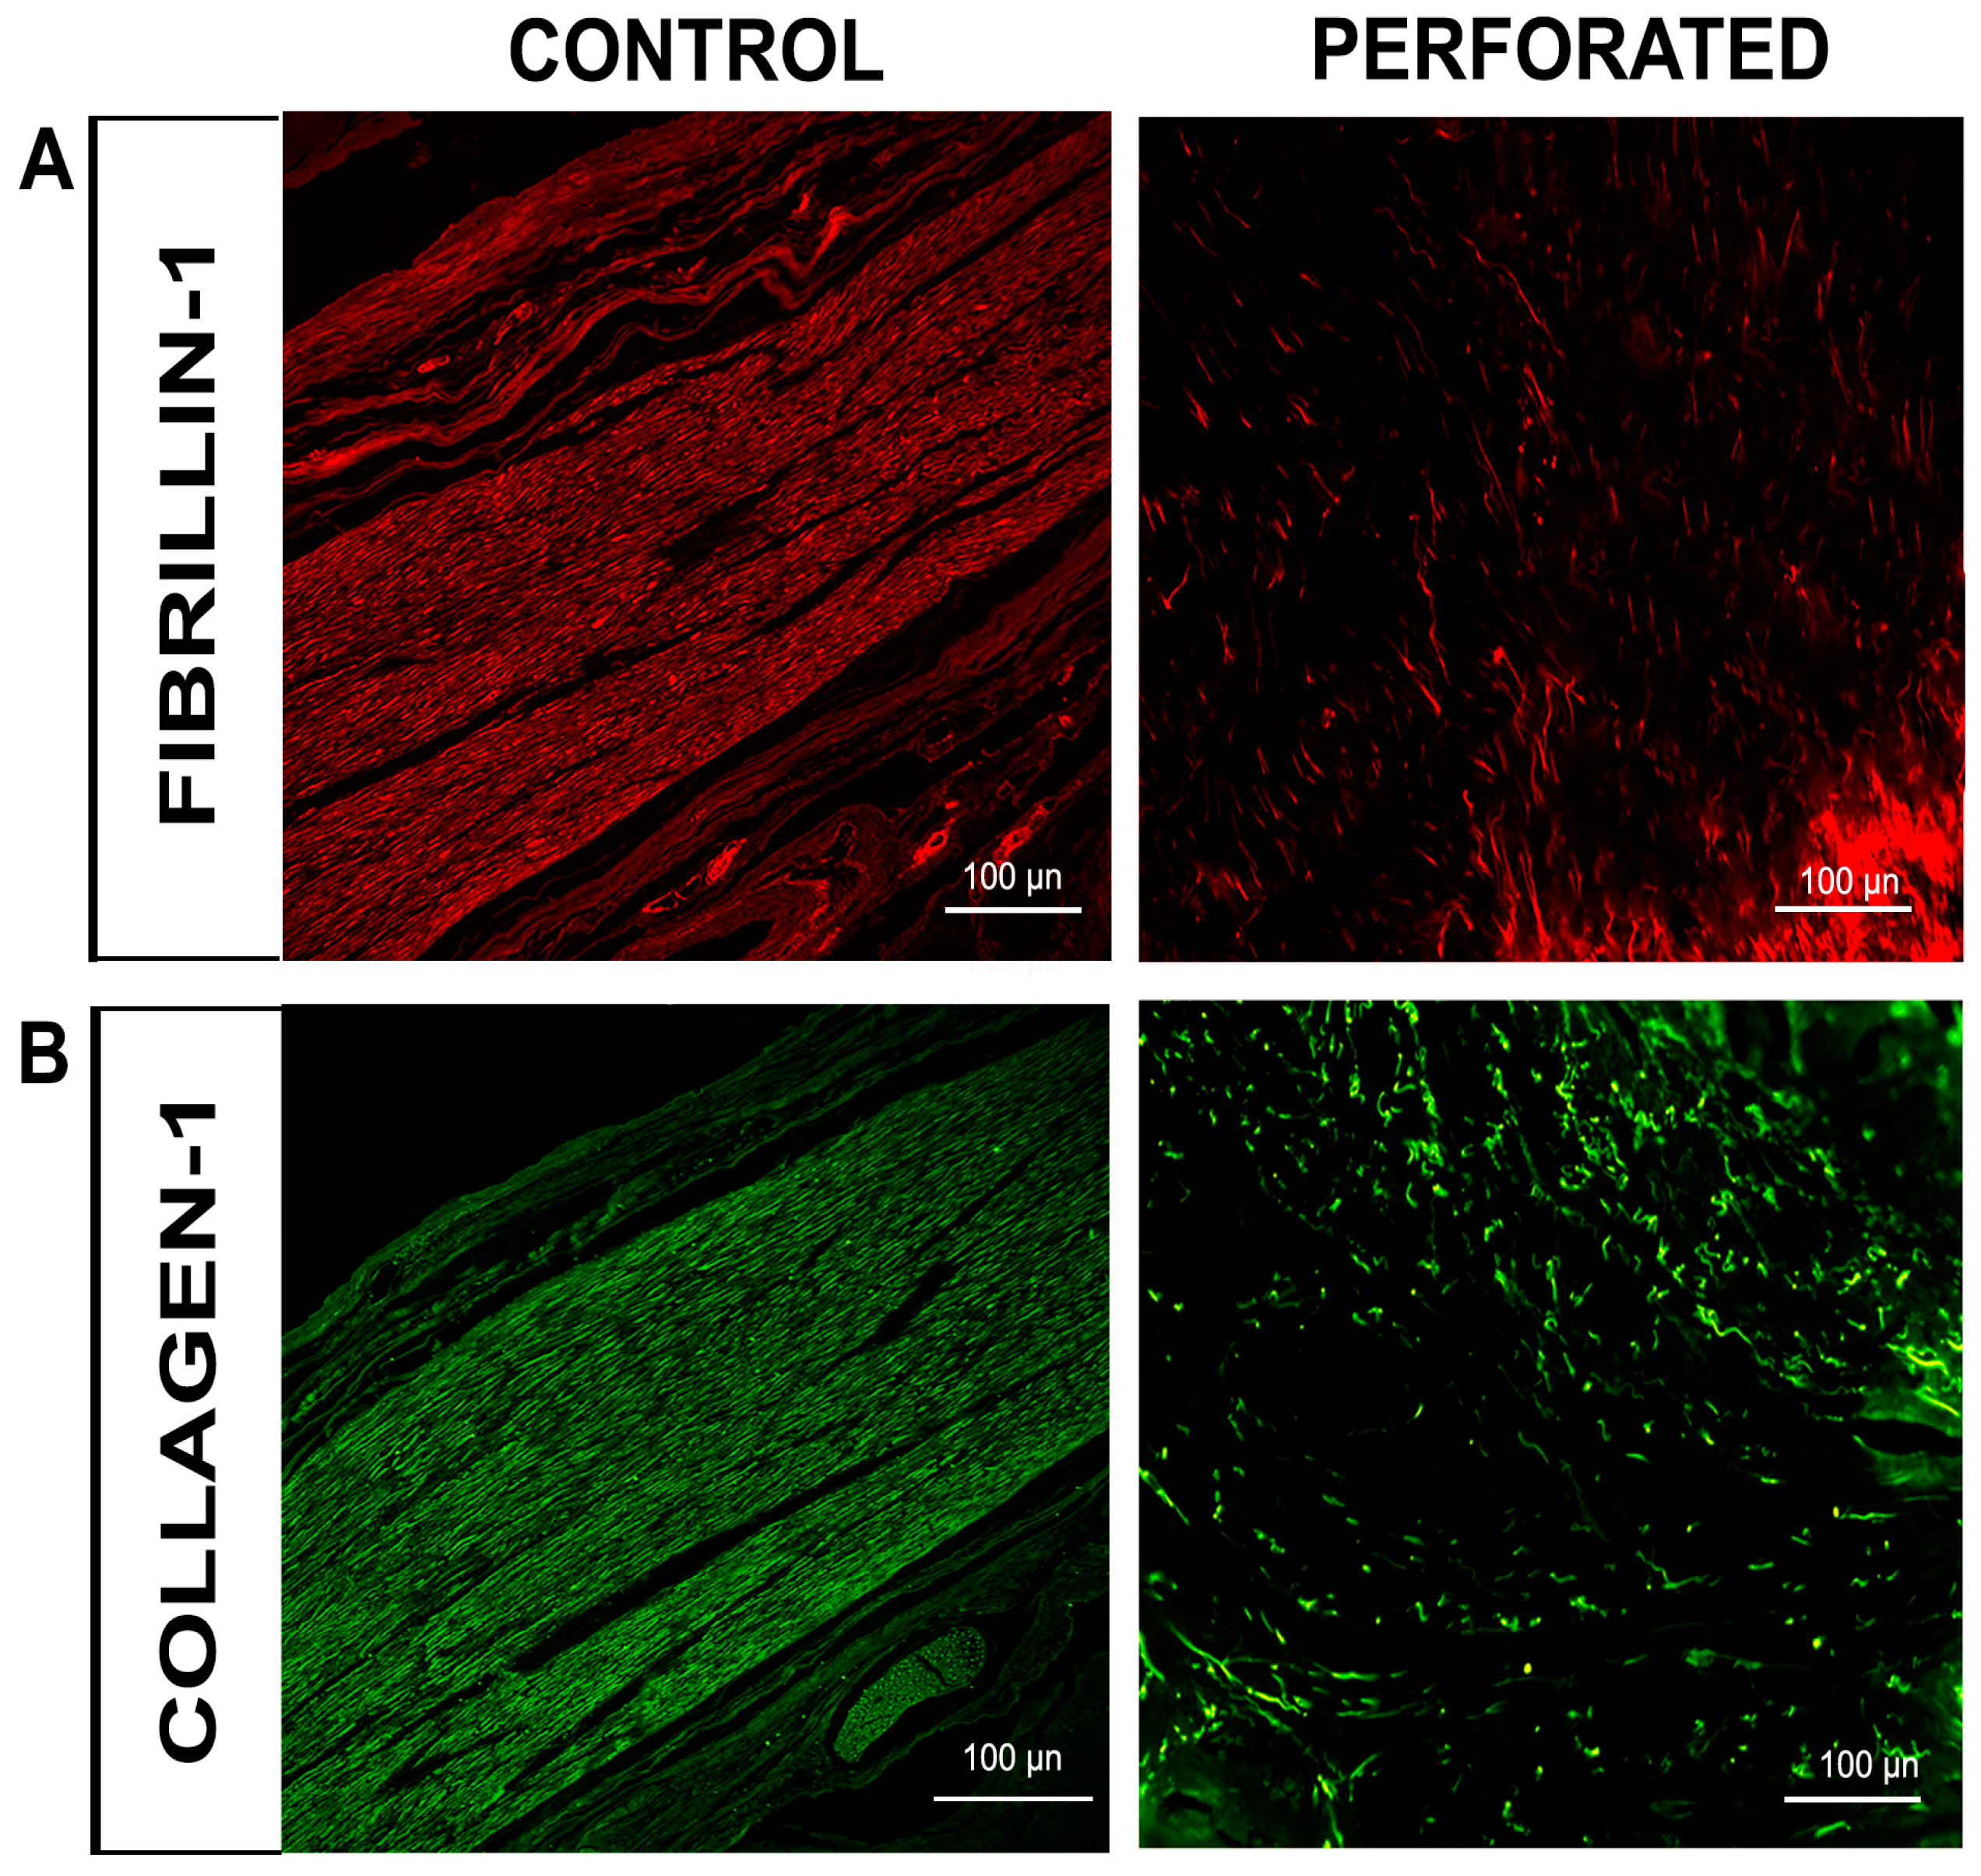

3.2. Immunofluorescence Evaluation